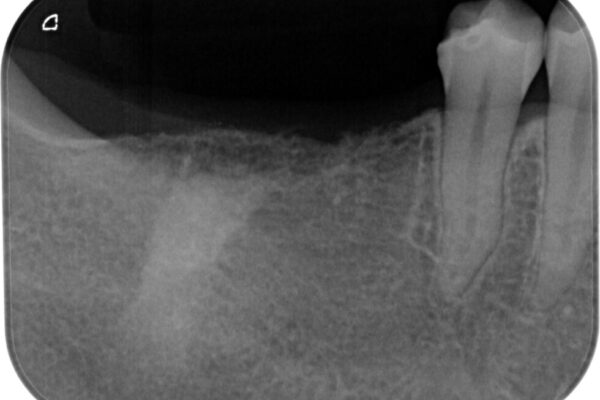

インプラント希望部位は右下第一大臼歯と第二大臼歯です。

しかし、噛み合わせの相手である右上の第二大臼歯が、長期間噛み合う歯がなかった影響で**挺出(歯が下に伸びてくる状態)してしまっており、このままではインプラントを埋入して被せもの(上部構造)を入れるためのスペースが不足している状態でした。

そこで、右上の奥歯に部分的なワイヤーを装着し、さらに矯正用アンカースクリュー(TADs)を併用することで、挺出した歯を圧下(歯を元の高さに戻す動き)させ、下顎にインプラントを埋入するための十分な垂直的スペースを確保しました。

• 挺出歯を圧下してスペースを確保!目立たない部分矯正で下顎大臼歯にインプラント治療を実現 治療前画像